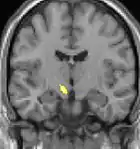

Neuro-imagerie

La tomographie par émission de positons (TEP) montre les zones du cerveau étant activées durant la douleur

La morphométrie voxel par voxel (VBM) montre les différences structurelles des zones du cerveau

Les images par tomographie à émission de positron indiquent les régions du cerveau qui sont activées lors de la douleur, par rapport aux périodes sans douleur. Elles montrent les régions du cerveau qui sont toujours actives durant la douleur en jaune/orange (appelé "matrice-douleur"). La zone au centre (dans les trois vues) est spécifiquement activée uniquement pendant la crise. Les photos sur la ligne du bas (effectuées par VBM) montrent les différences structurelles entre les patients souffrant d'AVF et des personnes saines : seulement une partie de l'hypothalamus est différente[50],[51].

Il semble exister des anomalies microstructurales hypothalamiques bilatérales (en l'occurrence l'existence d'une hypertrophie)[52] sans que l'on sache si ces anomalies sont la cause ou la conséquence de la répétition des crises.